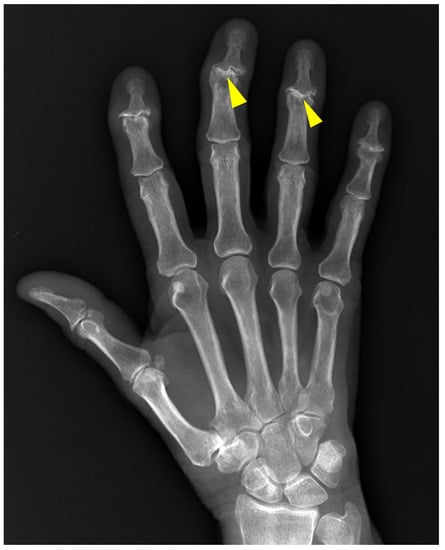

5. Psoriatic Arthritis (PsA)